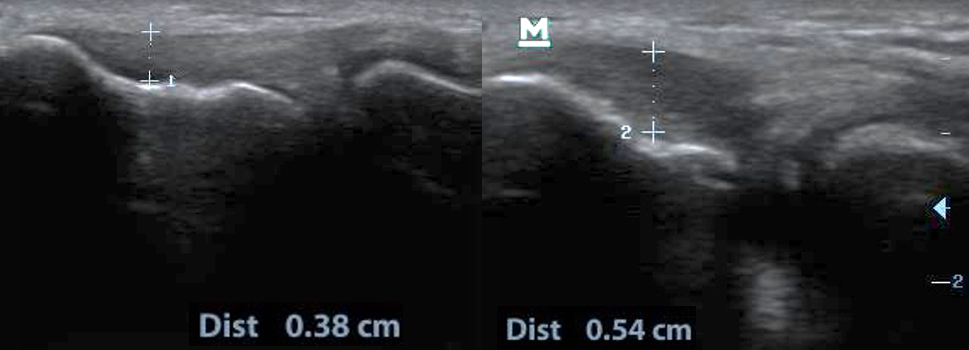

Diagnostyka funkcjonalna łokcia tenisisty w połączeniu z historią objawów jest dość prosta. Pacjent zgłasza dolegliwości bólowe okolicy nadkłykcia bocznego najczęściej po przeciążeniu. Ból reprodukowany jest podczas palpacji i napięcia izometrycznego lub ekscentrycznego. Proste testy ortopedyczne, takie jak: chair lift test, test Cozena, Test Milla czy test Thomasona, pozwalają na rozpoznanie tendinopatii okolicy nadkłykcia bocznego kości ramiennej. Dodatkowo można rozszerzyć diagnostykę o badanie ultrasonograficzne (USG), które według zaleceń European Society of Musculoskeletal Radiology powinno być wykonywane bilateralnie w pozycji siedzącej w maksymalnej pronacji i 90 st. zgięcia stawu łokciowego. Ocenie podlega grubość ścięgna, występowanie skupionych obszarów hipoechogenicznych (zdj. 2).